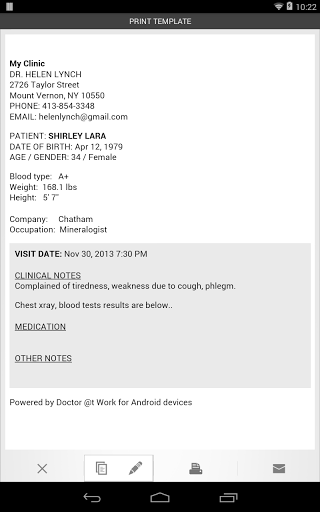

• Envoyer le résumé de la visite au patient par email ou SMS

• Personnalisez les informations patient que vous souhaitez capturer